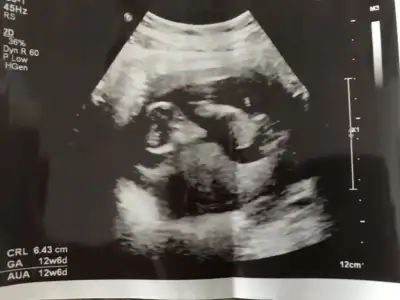

Ben yarım saat önce çikolata yemiştim bi sn durmadı hoplaya zıplaya denemdeiyseniz bir deneyin denerim 11+5 te erkek dedi doktorum o kadar net gördüm dedi görüntü durdurup bize gösterdiHayirli olsun bebebisin canim. Ilk kacinci haftada tahminde bulundu canim doktorun ya bizim daha hic gostermedi tahmin bile yok gidip geliyoruz bir heycanla esimle ama keyifci capraz yapmis bacaklari el ense yatiyo![]()